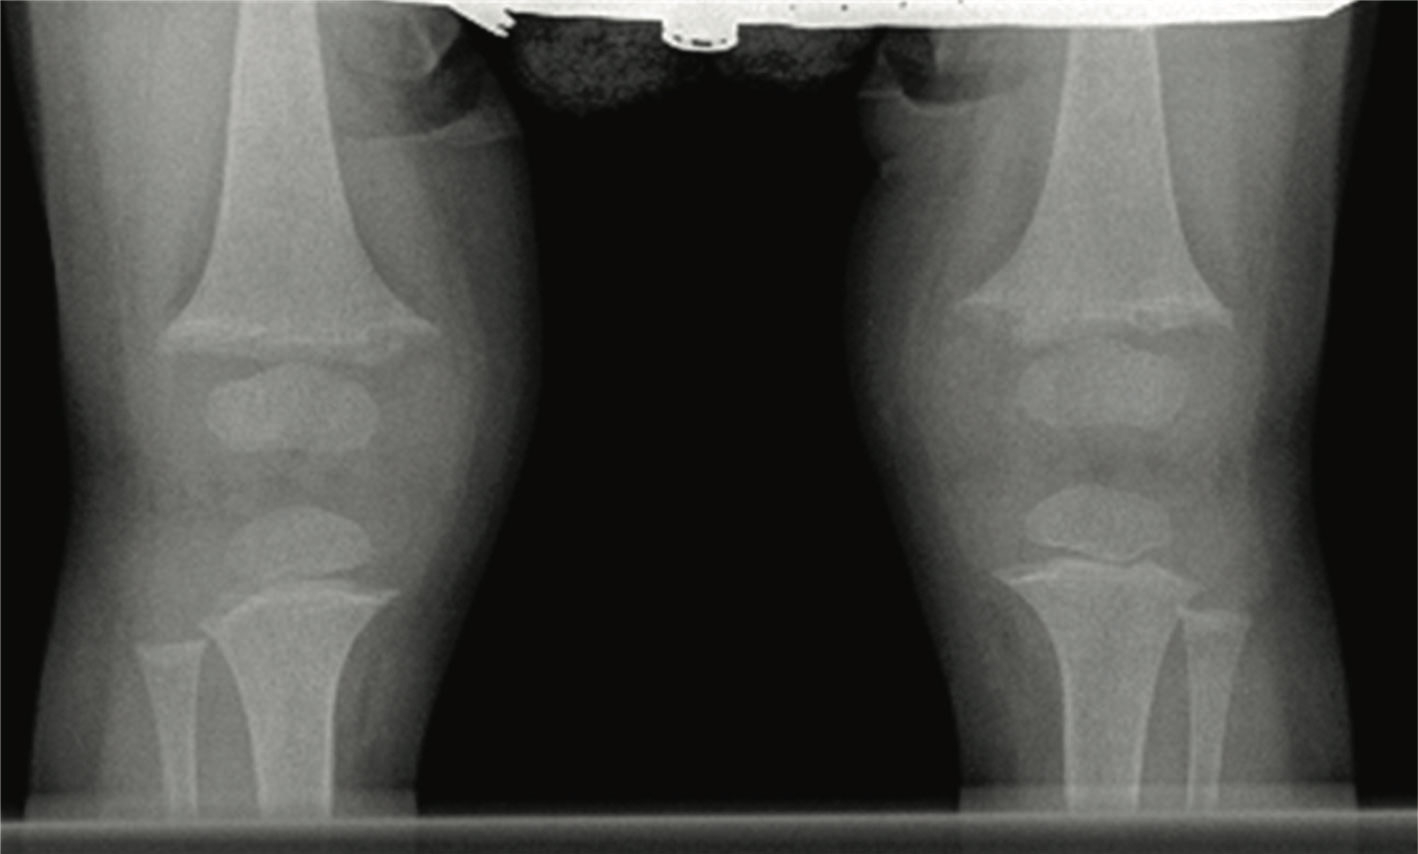

A female patient, second child of nonrelated parents was born at 39 weeks’ gestation after a normal uncomplicated pregnancy and a normal spontaneous vaginal delivery. Her birth weight was 4.1 kg. She developed genu varum around age 1 year. Biochemical studies showed normal serum calcium, low serum phosphorus, significantly elevated alkaline phosphatase (ALP), and parathyroid hormone (PTH) levels.

Radiographic studies of knee and wrist joints are showed in the upper figure. She was treated with ergocalciferol at various doses for 2 years with no improvement. Her serum 25 hydroxy vitamin D increased from 22 ng/mL at baseline to 80 ng/mL after a megadose of ergocalciferol. Repeat radiographs of her knees at age 3 years showed increased widening of epiphyses with increased cupping and fraying of the metaphyses (lower figure). She had complaints of polyuria, polydipsia, enuresis, and bone pain.